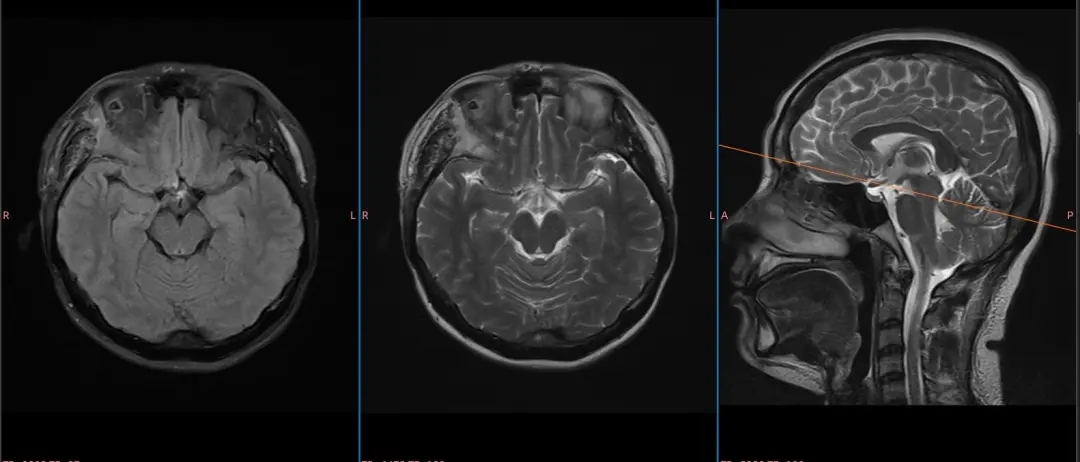

术后影像